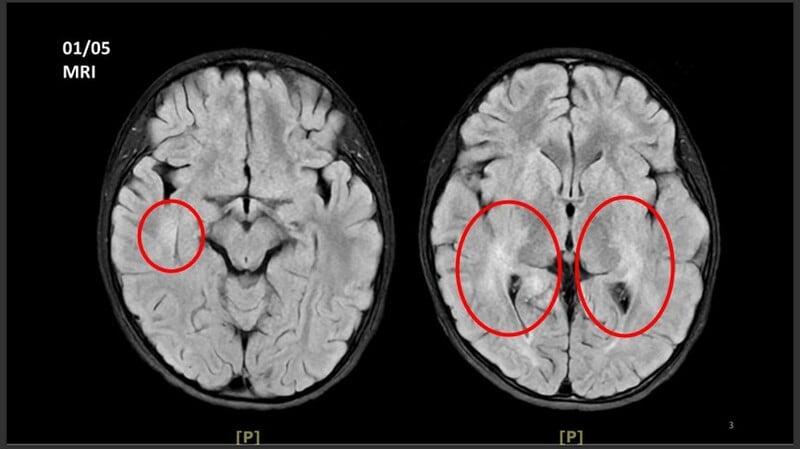

王傳育主任指出,女童當時血壓明顯偏高,心跳也較慢,醫療團隊擔心已有腦壓升高或顱內病變,立即安排住院,並同步給予降低腦壓治療與核磁共振掃描。檢查結果顯示,小腦、視丘及大腦白質、皮質下都可見異常訊號,符合急性散播性腦脊髓炎的影像表現。